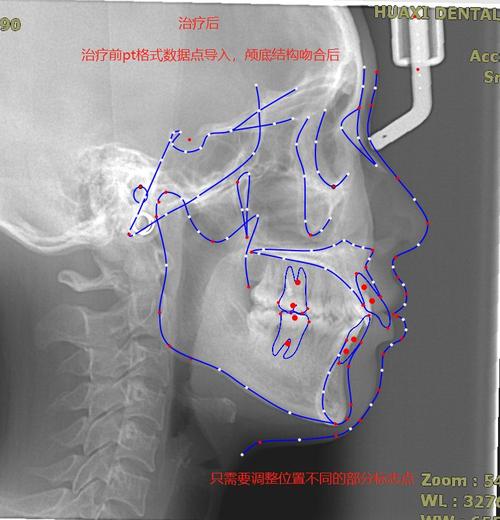

关键点标记(定点):

(图片来源网络,侵删)- 核心功能: 在头颅侧位片上精确标记一系列预定义的解剖标志点(定点)。

- 常见标志点: Sella (S), Nasion (N), A点 (A), B点 (B), Pogonion (Pg), Menton (Me), Gnathion (Gn), Gonion (Go), Articulare (Ar), Porion (Po), Orbitale (Or), Point A (A), Point B (B), Incisal Edge (I1, I2), etc. 不同软件或分析体系(如Downs, Steiner, Tweed, Wits, Ricketts等)可能要求标记的点略有不同。

- 手动定点: 医生用鼠标或触控笔在屏幕上精确点击放置标志点。

- 半自动/辅助定点: 软件利用图像识别算法(AI)尝试自动识别某些点(如鼻根、下颌角),医生再进行微调确认,这是目前的主流趋势,能显著提高速度和一致性。

- 可视化: 在图像上直接显示测量线、角度弧、距离标注等,直观展示结果。